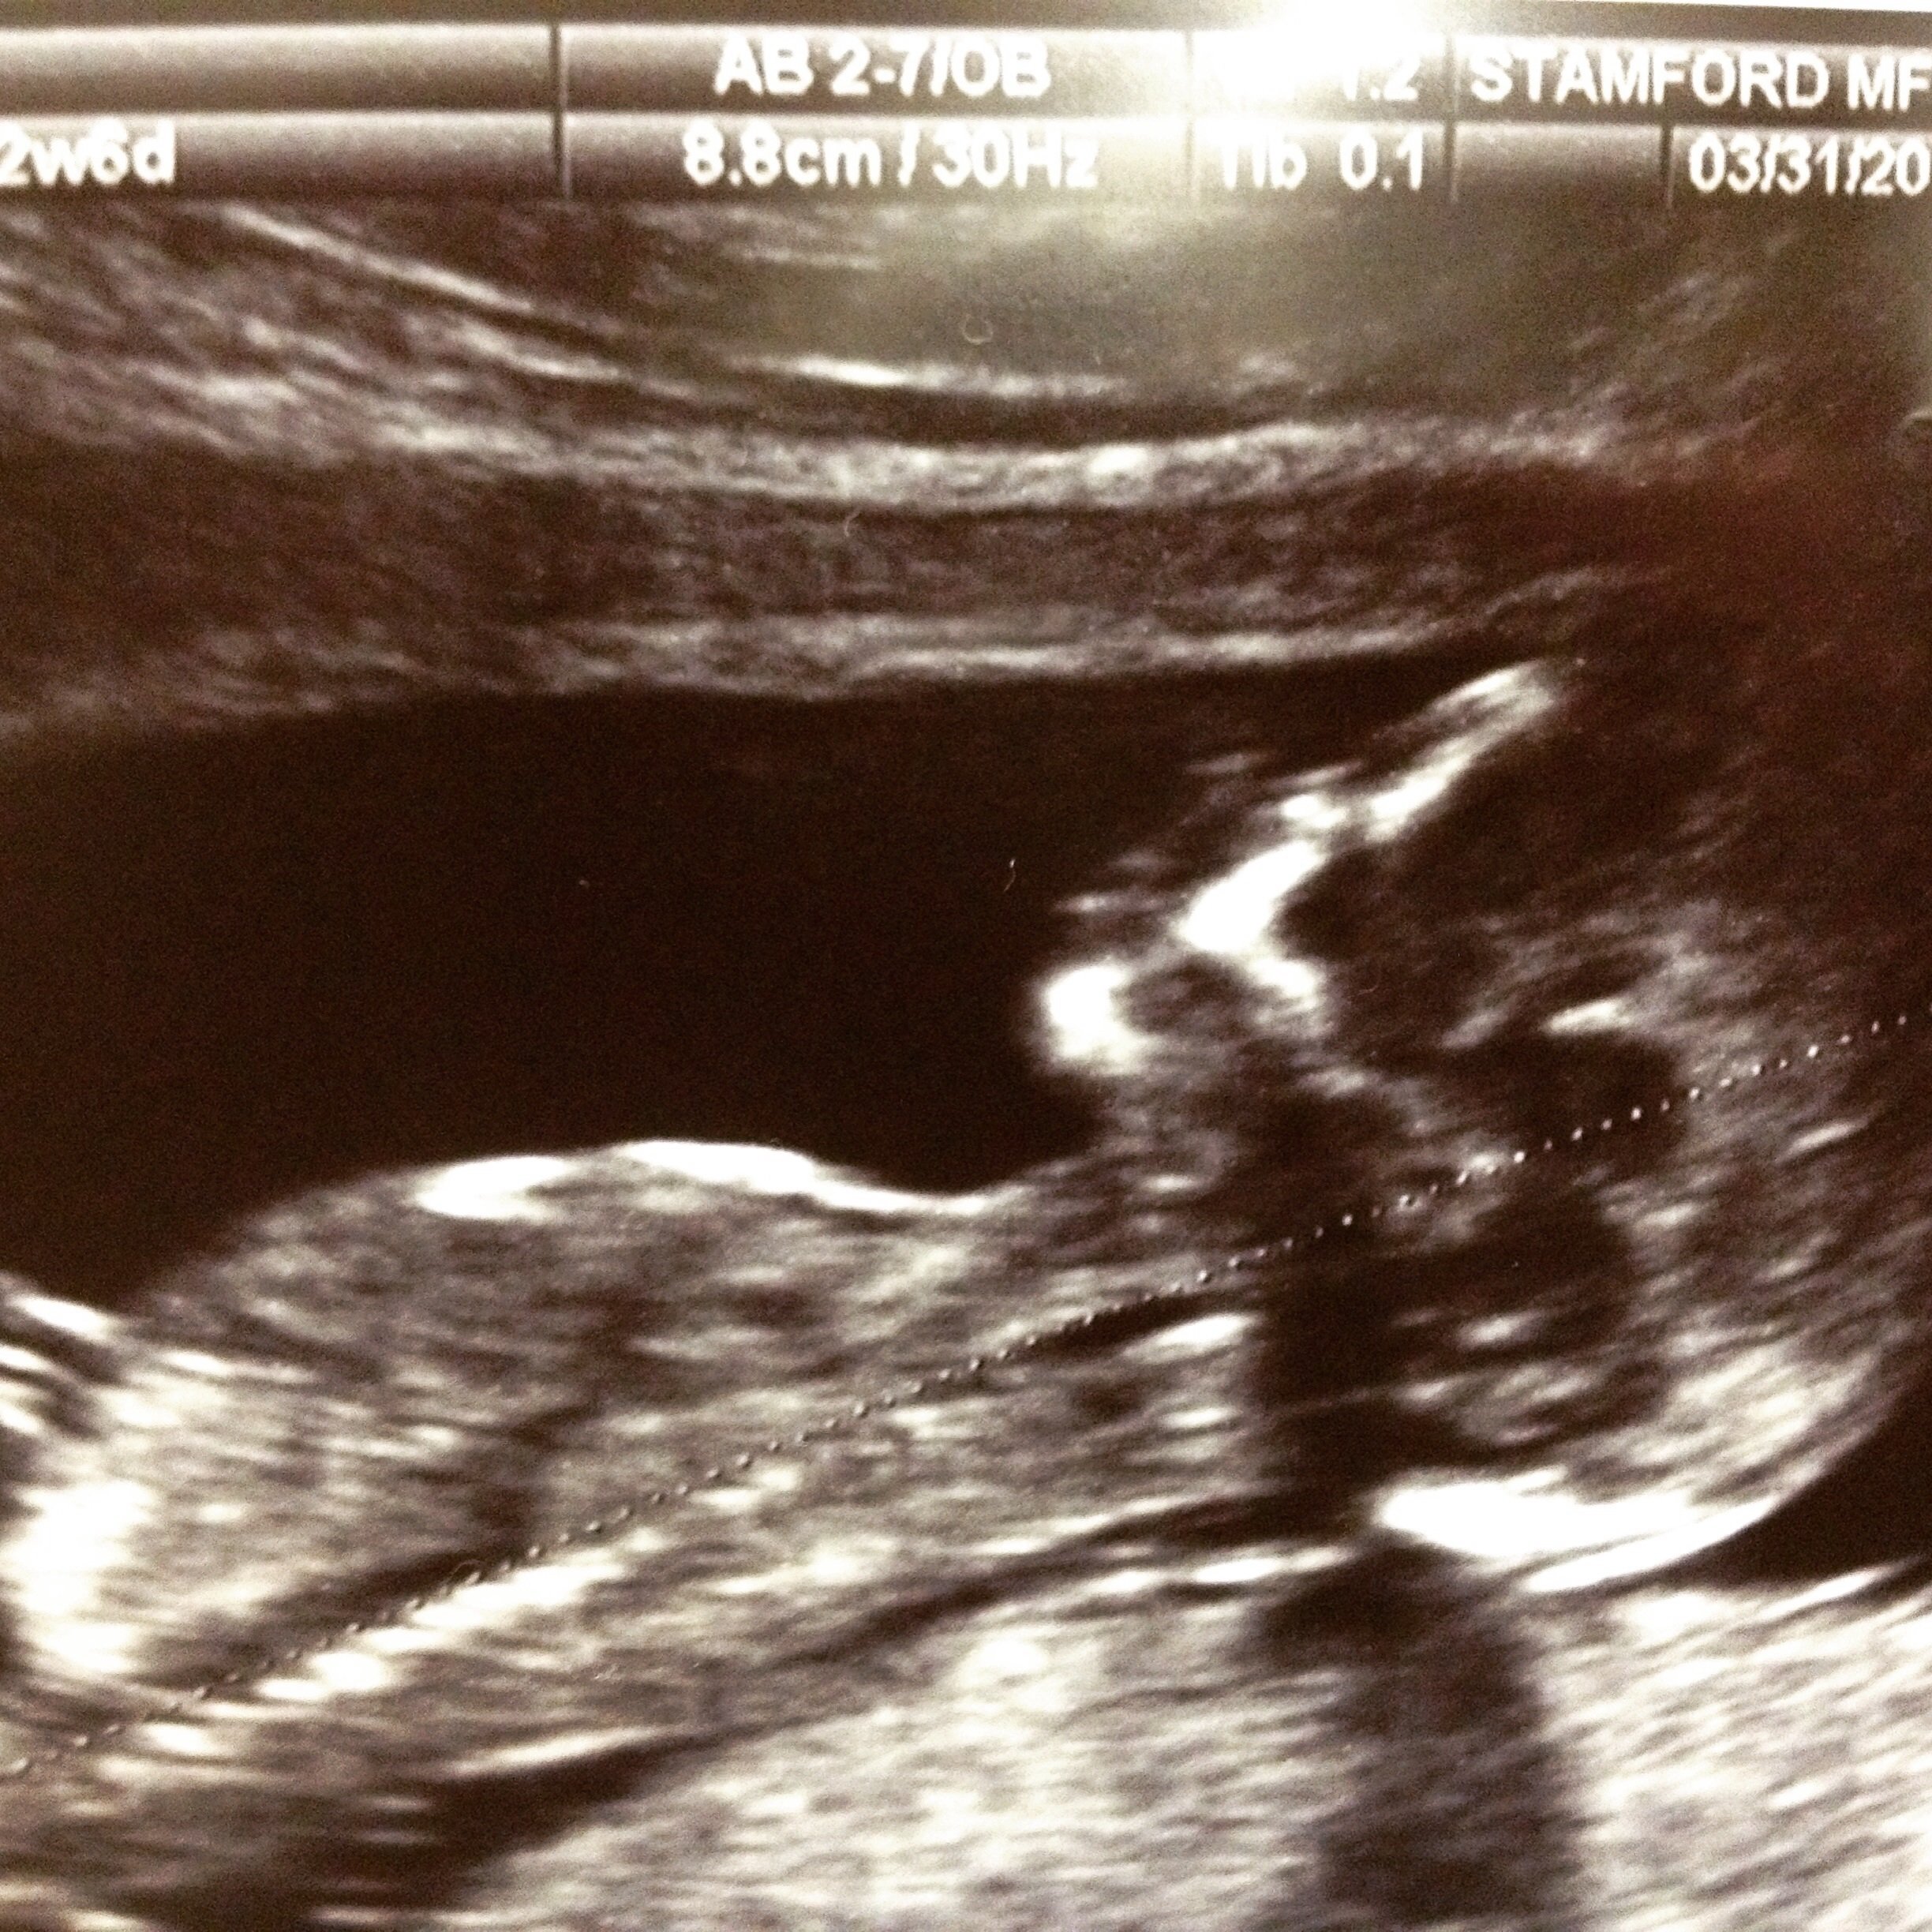

13 weeks 5 days for me! my due date got moved up to 10/2 last week after US showed baby was measuring a week ahead! he or she must be growing because i am absurdly hungry! i woke up at 5am to have a snack! i told my co-worker and she said "get used to it!!" sorry for all those still having symptoms... i have a lot more energy and my nausea is gone... can't say the same for my constipation though!!